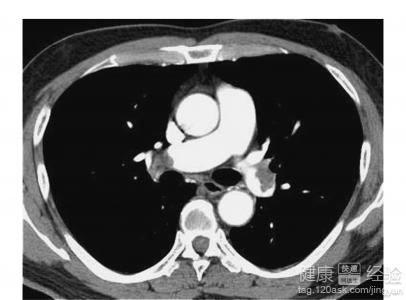

動脈栓塞,是指血塊或者進入血管內的異物稱為栓子,隨著血流的停頓在口徑相似較小的的周圍動脈或者內髒動脈的動脈內,造成血流障礙。動脈栓塞,一般是由於栓塞、血管收縮、血管痙攣、動脈瘤引起。動脈栓塞主要是因為血栓導致,除此之外,腫瘤、空氣、脂肪等異物也有可能會成為栓子。血栓大部分會來源於心髒,經常見於風濕性心髒病、心房顫動和心肌梗塞等。血栓所導致的栓塞,經常發生於心血管病人。

2動脈栓塞的發病症狀。動脈栓塞的早期症狀是間歇性跛行,遠側動脈博動減弱或者消失。疼痛可能會發生在下腰,臀、髂、大腿後側或小腿腓腸肌部位;還會發生與小腿肌群,在肢體慢性缺血時,皮膚萎縮變薄、發亮等。